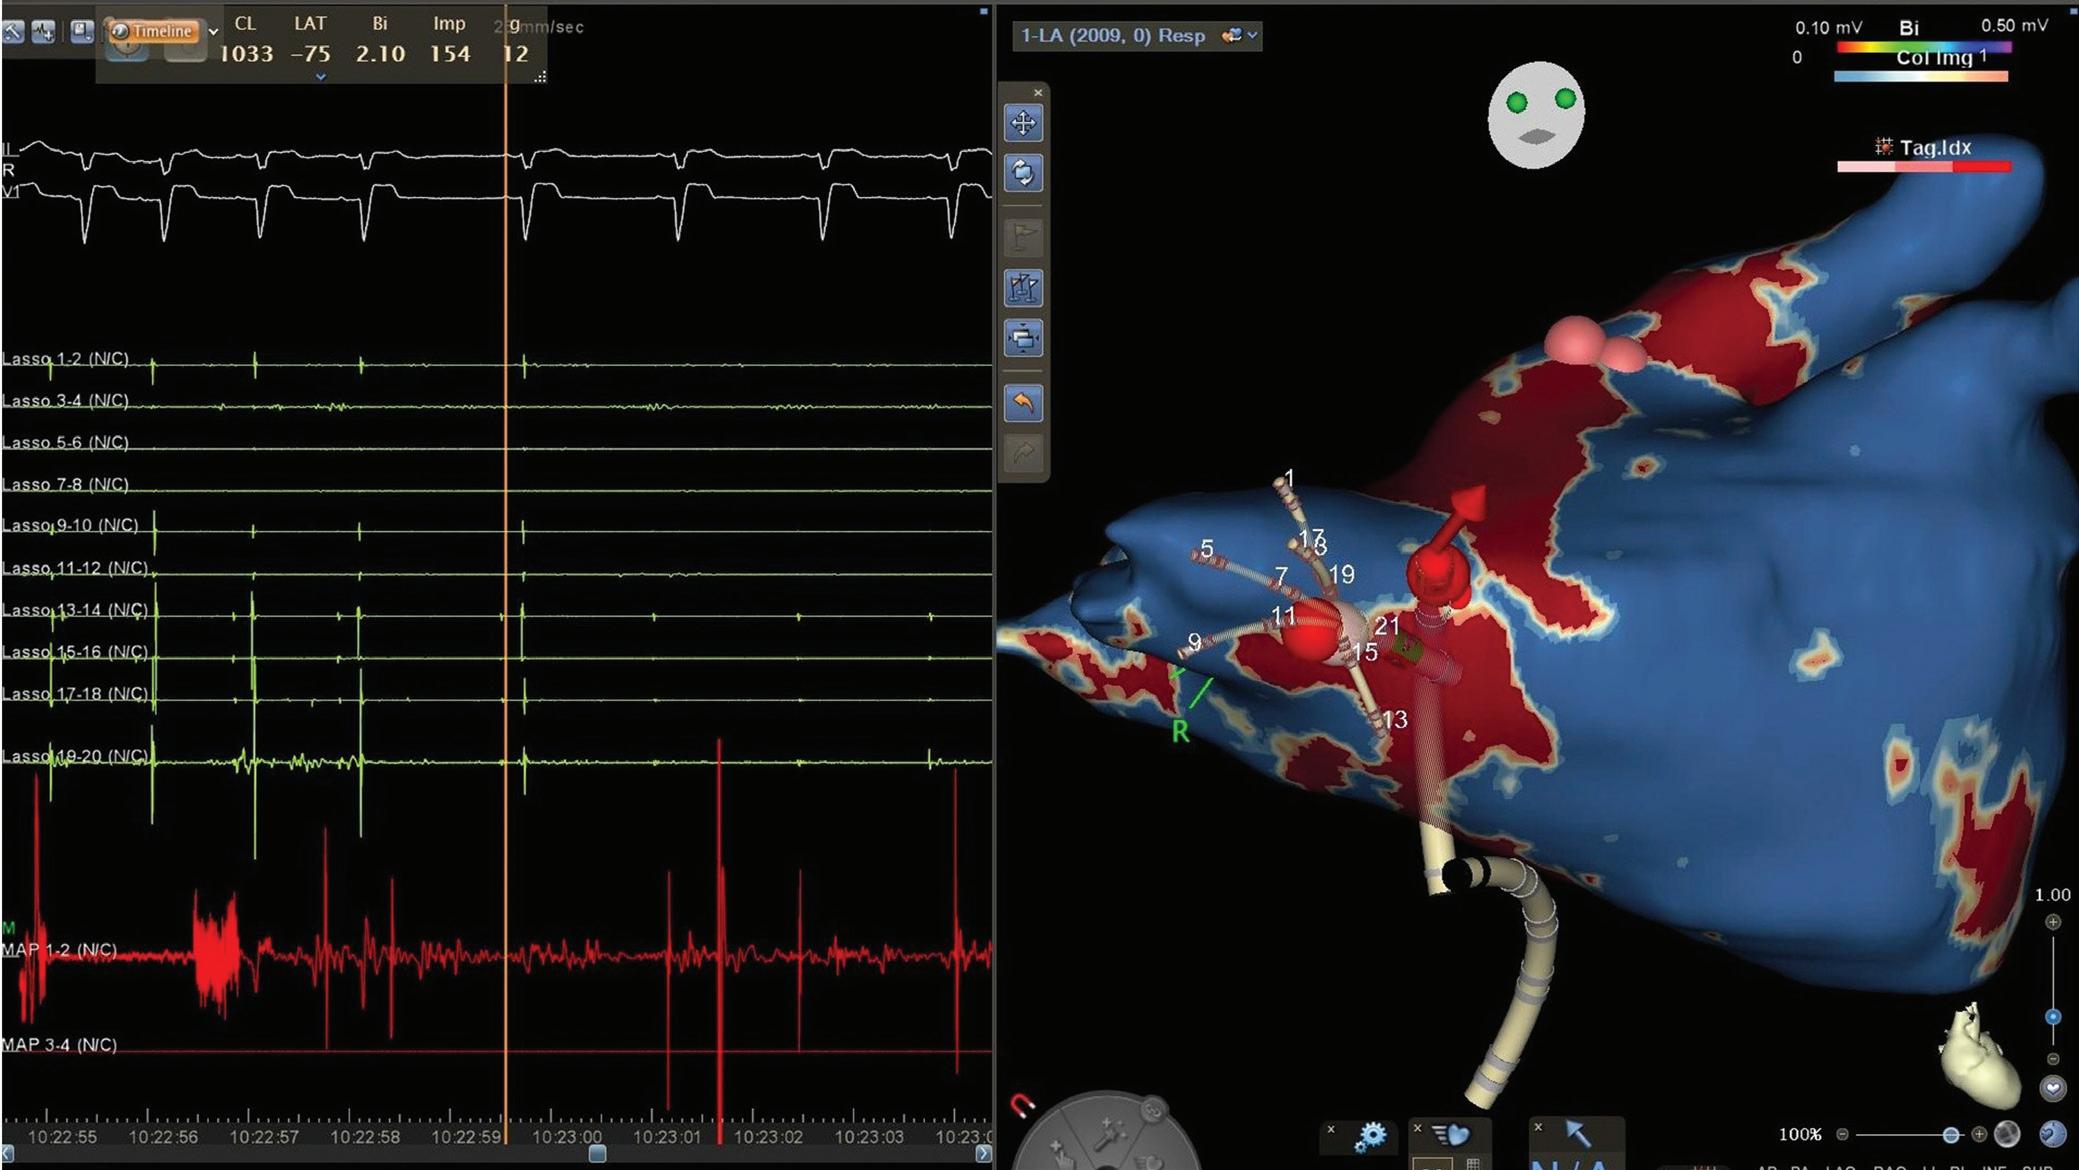

Figure 3: Agreement Between Electroanatomical Mapping and 3 Months Late Gadolinium Enhancement-MRI Regarding Gap Localisation

LGE-MRI-guided Repeat Ablation

Accumulating evidence indicates that LGE-MRI can detect and localise the gaps in ablation lesions with high accuracy (Figure 3).5–7 14 Overall, the accuracy and in particular the high sensitivity in the detection of gaps appears to be sufficient for LGE-MRI-guided repeat ablation – not only in the context of AF (Figure 4), but also with respect to post-ablation reentrant atrial arrhythmias (Figure 5).5 7 14

LPV entry

RPV entry

Activation maps of the LPVs and RPVs with conduction vectors (CARTO 3, coherent mapping with Pentaray catheter, Biosense Webster) indicating the entry site of the activation wave front (functional gaps) as detected during a repeat ablation procedure. Corresponding gaps detected by prior late gadolinium enhancement (LGE)-MRI (3 months post index ablation) are displayed in the small boxes. Colour-coding of the LGE maps (ADAS 3D software) is based on image intensity ratios with thresholds for dense scar (>1.32 red) and border zone (1.2–1.32 yellow), respectively. White arrows indicate localised functional gaps and LGE discontinuities, respectively. LPV = left pulmonary vein; RPV = right pulmonary vein.